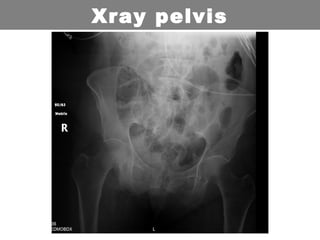

• 65 years old Female

• Alert: Possible pelvic fractures

• Initially hypotensive. Stable in ED.

• FAST scan Negative

• Xray and CT: Nil

• Poly trauma: Open fractured ankles

Trauma Call: 002

Xray pelvis